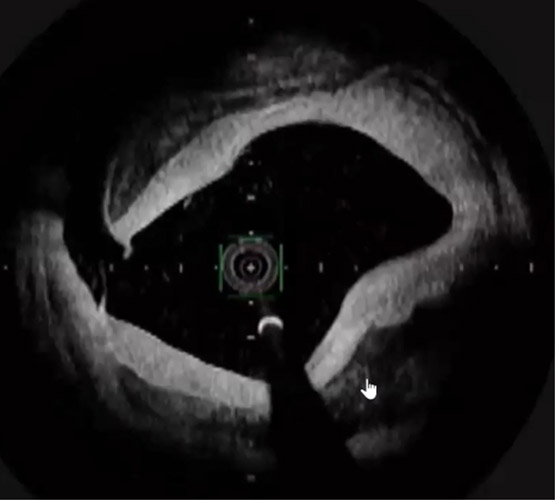

ガイディングシースから造影を行い、SFAの石灰化を伴う短いCTO病変を確認した(図6)。6gワイヤーで石灰化を縫うようにdrillngをし、ワイヤー通過に成功した。血管狭窄部貫通用カテーテルでCTO部分を通過させた後に、4㎜径のバルーンで拡張を行った。OFDIで血管内を観察すると突出する石灰化及び、Distal部分は解離を認めた(図7)がルーメンは確保出来ていた。石灰化部分に4㎜径のcutting balloonで拡張を追加しルーメンは確保(図8)できたが、圧較差は改善しなかったため更にProximal側の病変(図9)に4㎜径のcutting balloonで拡張しDES 7㎜×150㎜を留置した。Distal側はDCB 4㎜×200㎜を施行した。最終造影では病変部は拡張出来ており、圧較差がなくなったことを確認し終了した。(図10)今回の様にPTAは開通しているがATAは閉塞している様な症例でTAIを行う際、PTAからシースを挿入するとPTAも閉塞してしまいCLTIを招いてしまう恐れがある。今回の様な場合は閉塞しているATA経由のTAIを行うことが重要と考える。